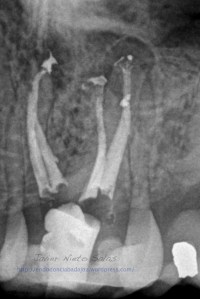

Nos llega un paciente con una PERIODONTITIS APICAL CRÓNICA, le realizamos el tratamiento de conductos, instrumentaríamos con sistema M-Two y obturaríamos con la técnica de Ola contínua de Buchanan y un backfilling con la pistola Obtura II. Se utilizó Microscopio Zeiss con luz xenón, y se han tomado las fotografías con una cámara Sony.

Como podemos ver, en las Rx finales, no afecta el ser conservadores con la estructura dentaria en el tratamiento y resultado final.